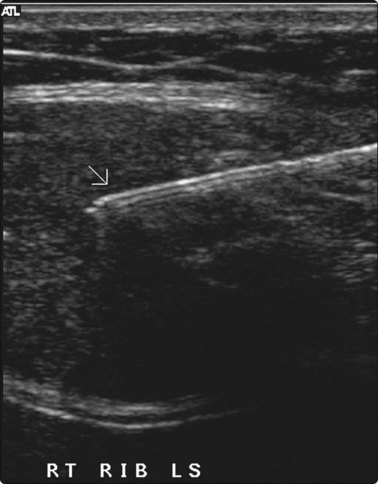

image

Fig. 3.1 Pancoast tumour biopsy

Care is required in positioning the patient for maximum comfort and access to the lesion to avoid ribs and scapula.